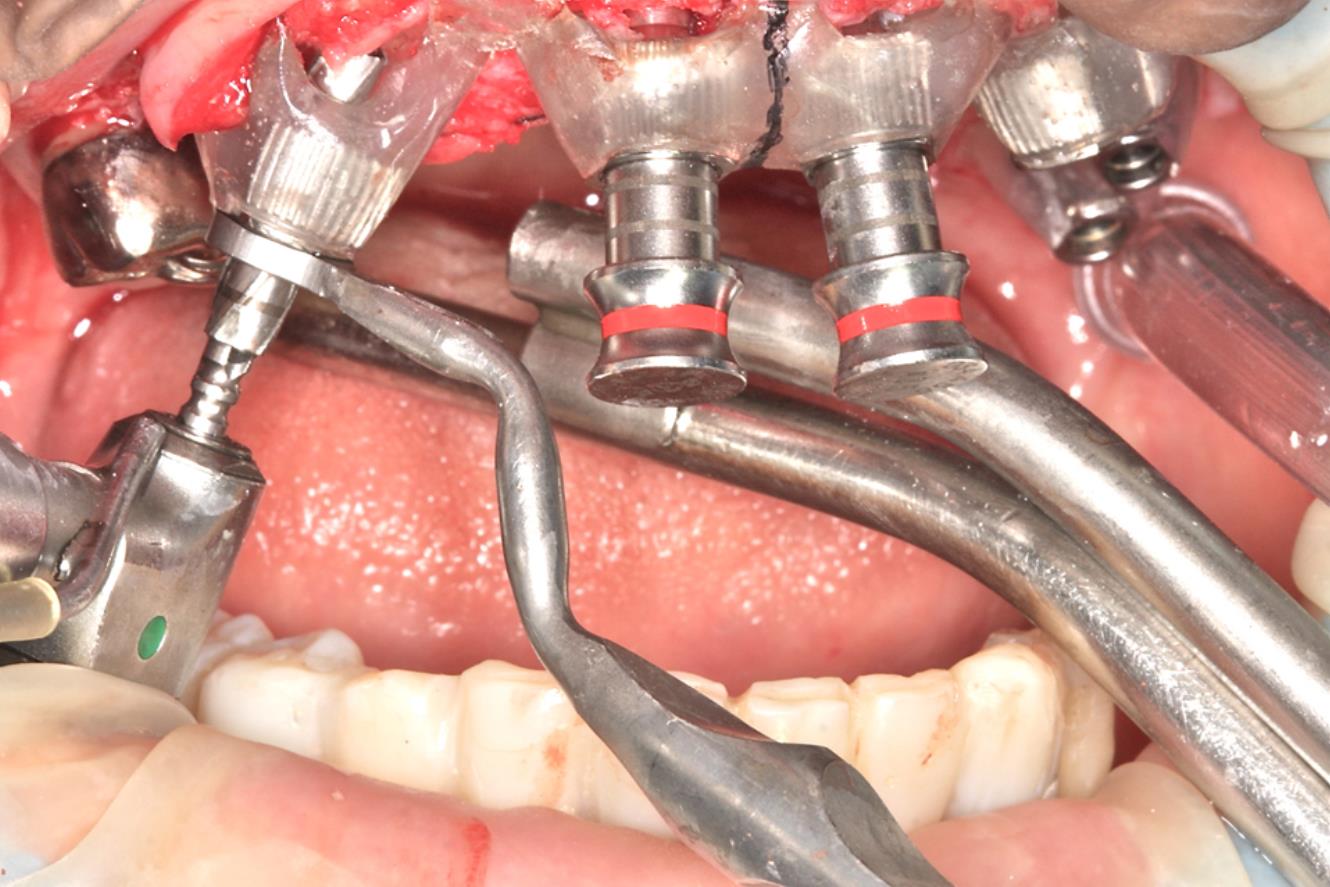

ガイドサージェリーのスターティングに また形成にもガイドの動揺を最小限にすることができる。ひいては所定の位置に近い埋入が可能になる

傾斜埋入の際の形成にもドリルのずれが無く、ガイドを揺さぶることも起こりにくい

フライスドリルは骨質の不均一な部位に応用する